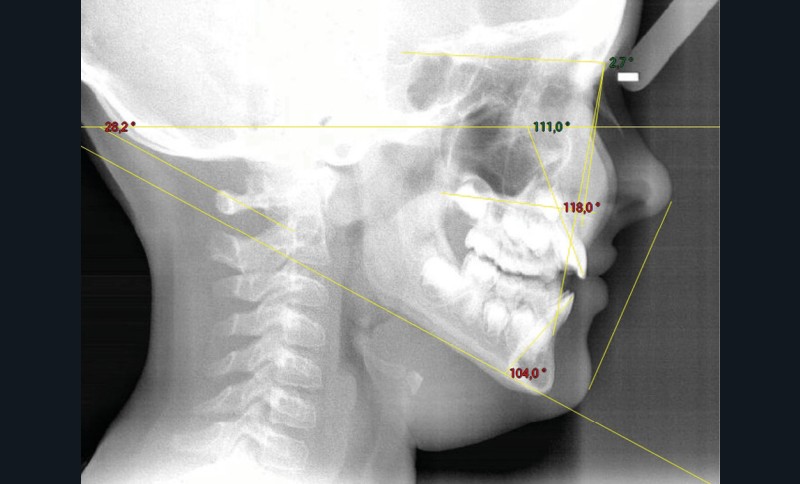

Quelques années plus tard, au moment de démarrer sa prise en charge orthodontique, la patiente présentait à nouveau une béance antérieure, un décalage des milieux incisifs de 2 mm et le problème transversal avait récidivé. Lors de l’examen clinique, elle présentait un inversé d’occlusion bilatéral postérieur et une ventilation buccale exclusive. À la suite du refus de réaliser l’amygdalectomie de façon précoce, elle ronflait toujours et sa déglutition ne s’était pas modifiée malgré des séances d’orthophonie (fig. 7 à 15).